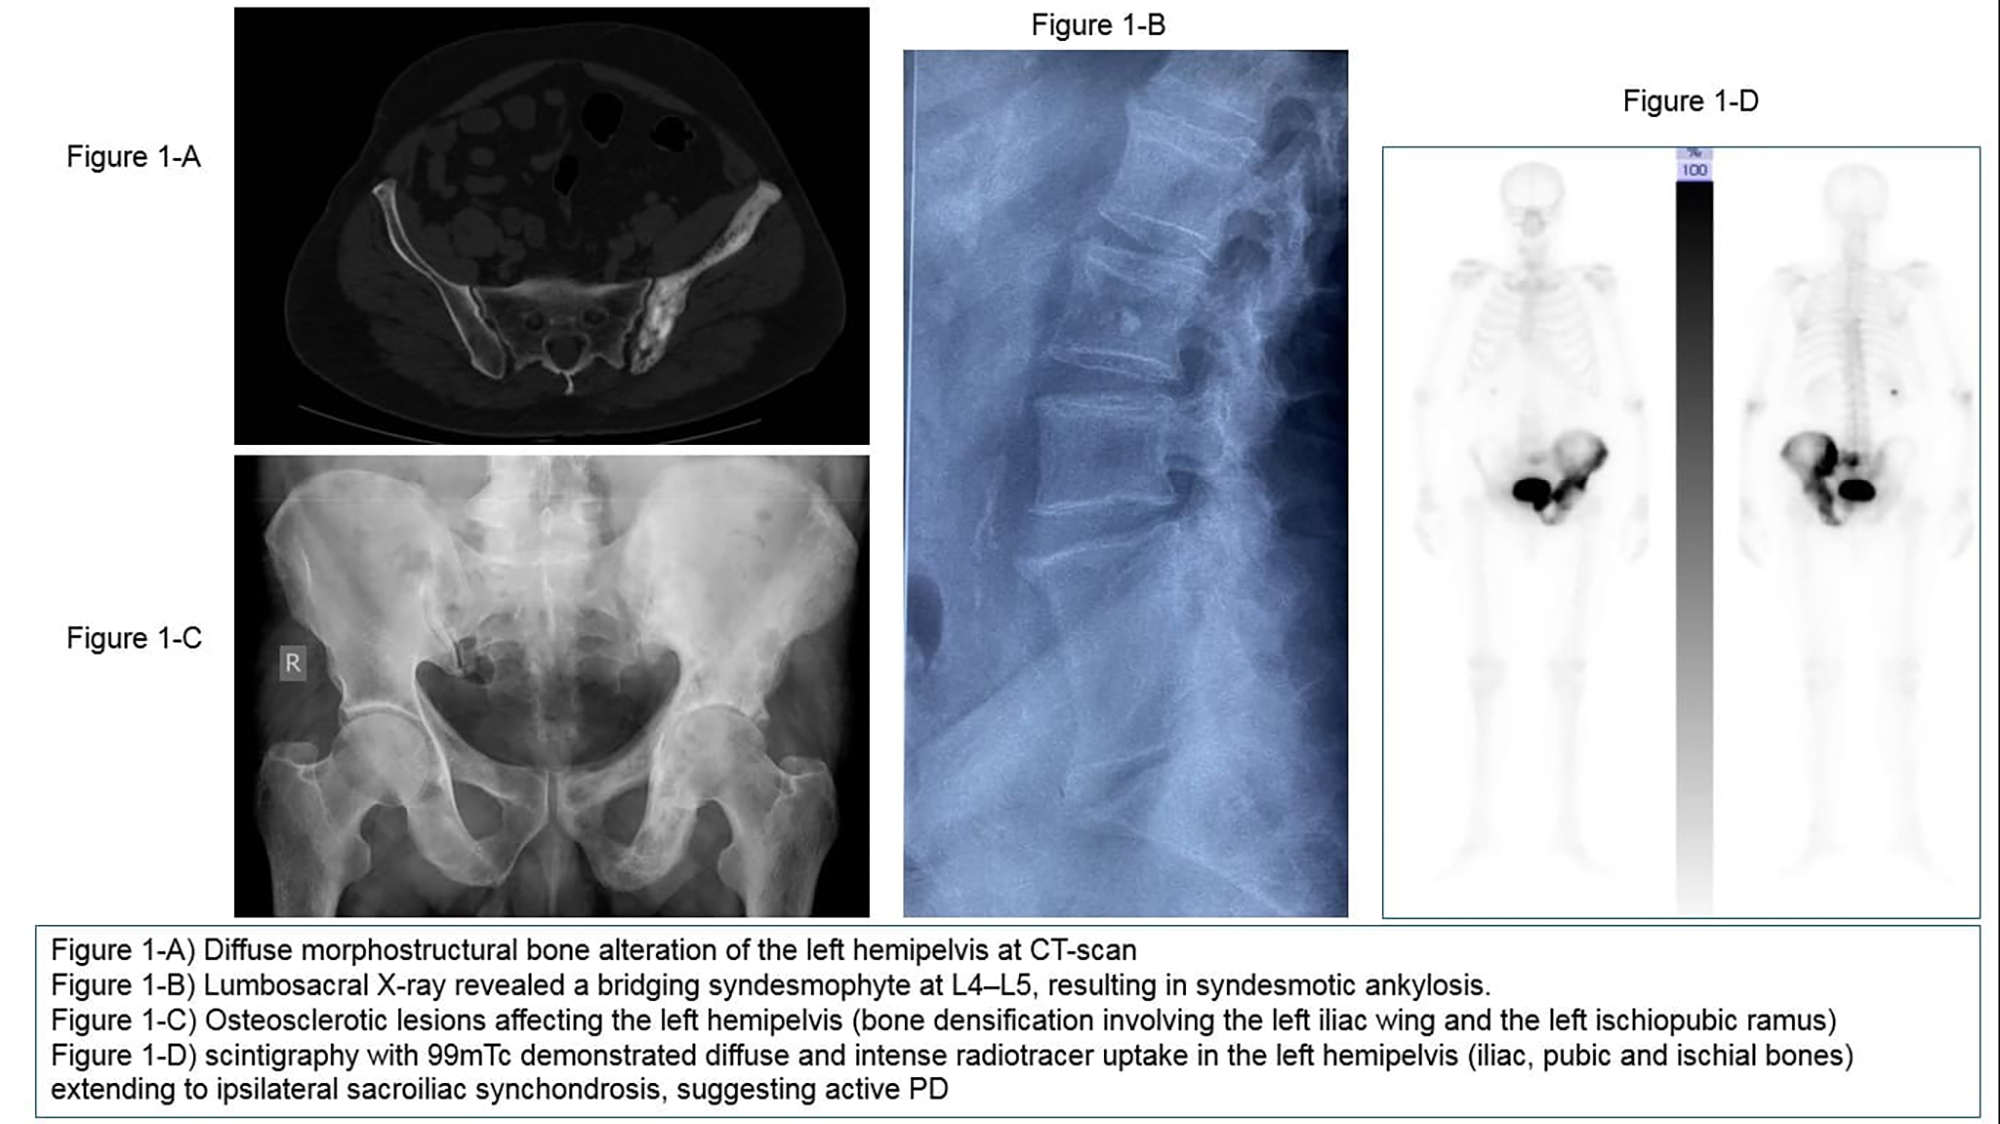

PO:11:170 | When Paget Meets Inflammatory Back Pain: A Diagnostic Dilemma Between Bone Remodeling and Spondyloarthritis